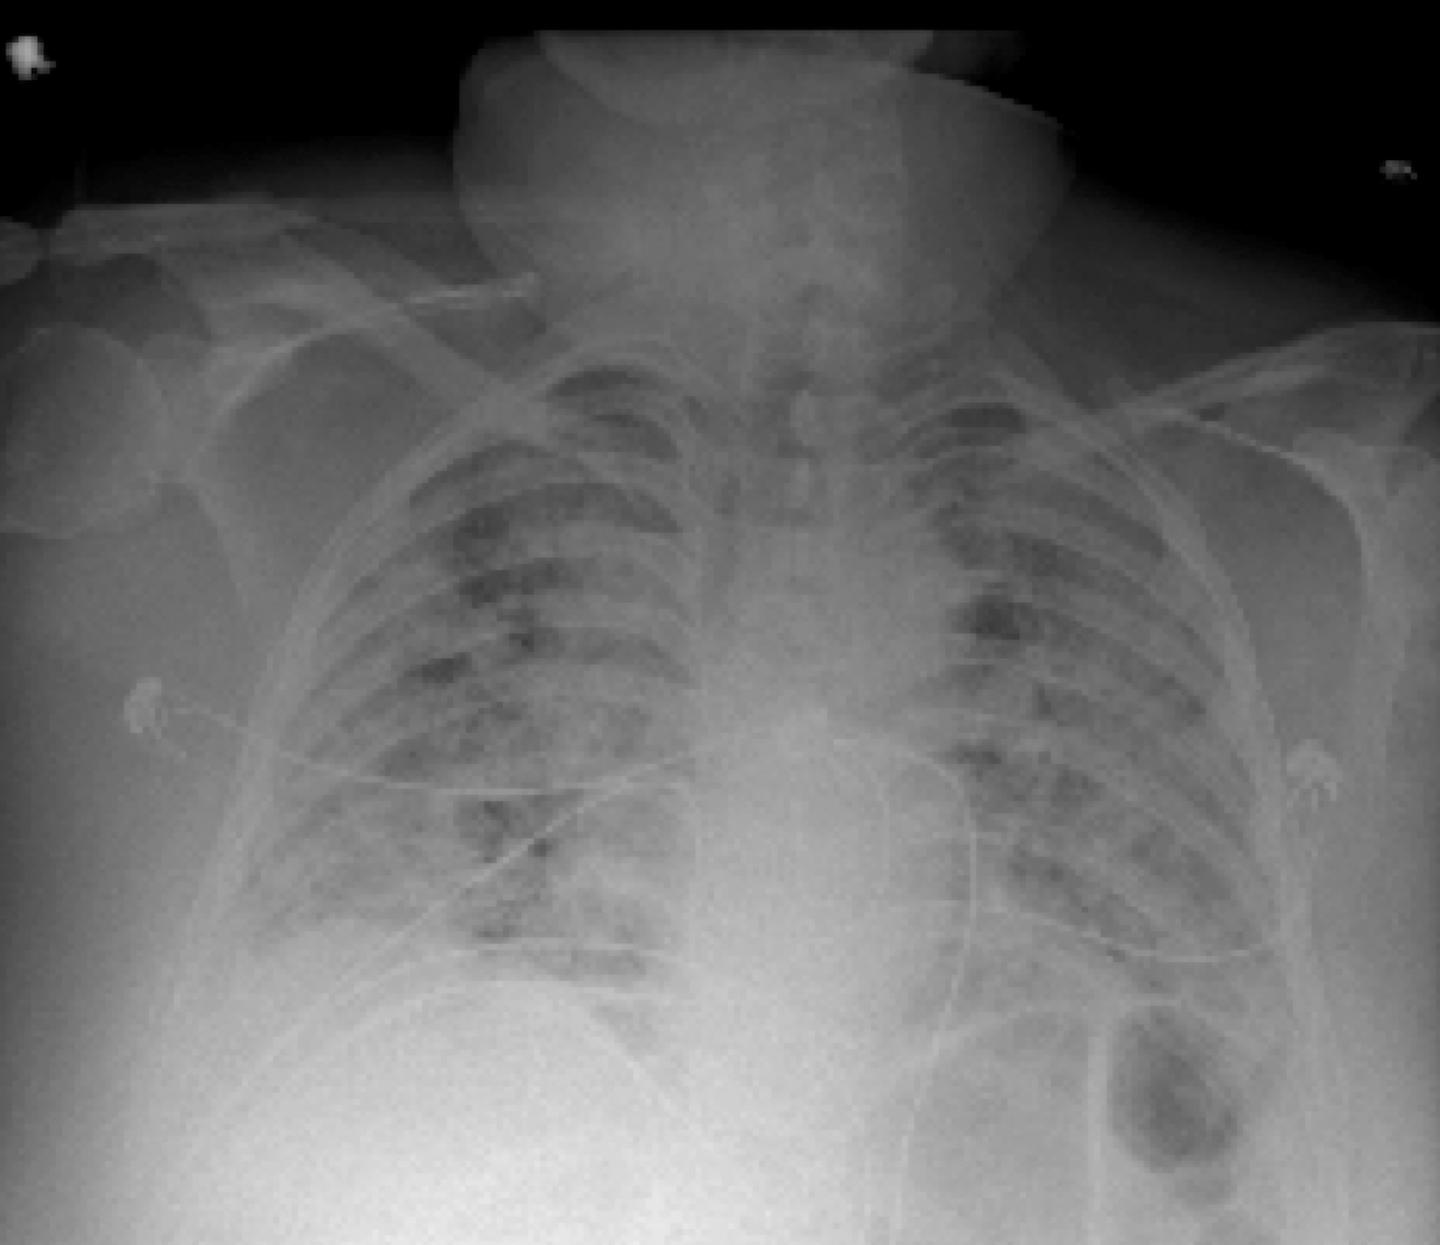

What Does White On A Chest X Ray Mean . For example, bones of the chest wall (ribs and vertebrae) may absorb more of. Structures that block radiation appear white, and structures that let radiation. Here are the visuals that suggest. Typically, these nodules are smaller than three 3 centimeters (cm) in diameter. This phenomenon, also known as. The lungs are normally black on a chest. This is a small, round growth on the lungs that shows up as a white spot on image scans.